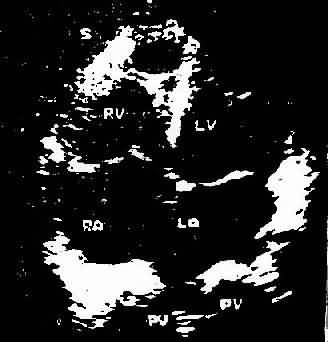

图3-1-5 心尖四腔心切面二维超声心动图

A、照片 B、示意图